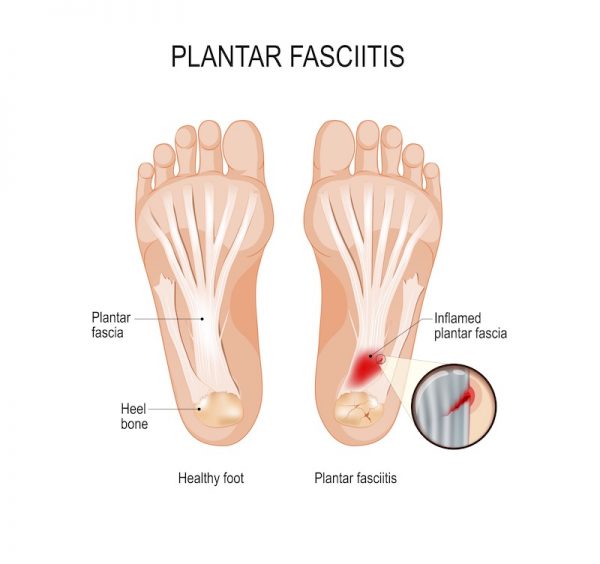

Heel Pain Causes Treatment and Prevention top, Do You Wake Up In The Morning With Excruciating Pain In Your Heels Sutherland Podiatry top, Causes of Morning Heel Pain in Arizona Fixing Feet PLLC top, Why Do I Have Heel Pain in the Morning SPORT Orthopedics top, Why Do I Have Heel Pain in the Morning Here s How to Relieve the Pain Feet Feet top, 5 Reasons You May be Experiencing Foot Pain in the Morning Foot and Ankle Group top, Why do my feet hurt when I wake up and walk top, Foot Pain In The Morning Causes Treatment top, Why Do My Heels Hurt in the Morning Northeast Foot and Ankle top, Heel Pain After Waking Up in the Morning Dr. Chetan Oswal Pune top, Early morning heel pain causes remedies prevention top, Heel Pain in the Morning Here s What It May Mean Advanced Foot Ankle Center Podiatry top, Heel Pain Plantar Fasciitis is a common and Painful Condition top, Heel Pain Causes Diagnosis Treatment top, Why Pain From Plantar Fasciitis Is Worse in the Morning top, Why does my heel hurt when I get up in the morning Catching Health with Diane Atwood top, The Consequences of Leaving Plantar Fasciitis Untreated Plantar Fasciitis top, It Hurts to Put Pressure on My Feet in the Mornings Premier Podiatry top, Plantar Fasciitis Orthopaedic Foot Ankle Surgeon Edinburgh Mr. H Shalaby top, Causes of Morning Heel Pain Blog top, The Do s and Don ts of Plantar Fasciitis Lucky Feet Shoes top, Pioneer Podiatry top, Why Plantar Fasciitis Feels Worse in the Morning Washington Foot Ankle Sports Medicine Podiatry top, How to Treat Your Morning Heel Pain at Home in 3 Easy Steps Foot Leg Centre top, Plantar Fasciitis Causes Symptoms Treatments and More top, Plantar fasciitis Plantar fasciitis is caused by aseptic inflammation of the plantar tendons or fascia. The most common symptoms are heel pain and discomfort often at the heel of the foot sometimes top, Heel pain or plantar fasciitis Treatment exercises and causes top, 4 Heel Pain Symptoms to Take Seriously Chicagoland Foot and Ankle Board Certified Foot and Ankle Specialists and Surgeons top, Plantar fasciitis Symptoms and causes Mayo Clinic top, What is Plantar Fasciitis Common Causes of Plantar Fasciitis top, Common Causes of Heel Pain top, Plantar Fasciitis and Bone Spurs OrthoInfo AAOS top, Plantar Fasciitis Symptoms and Treatment familydoctor top, 2 Major Causes of Heel Pain Leading Edge Physiotherapy St Albert Edmonton Physical Therapy top, Why Heel Pain Won t Disappear Foot and Ankle Podiatrists top.

Heel pain worse in morning top